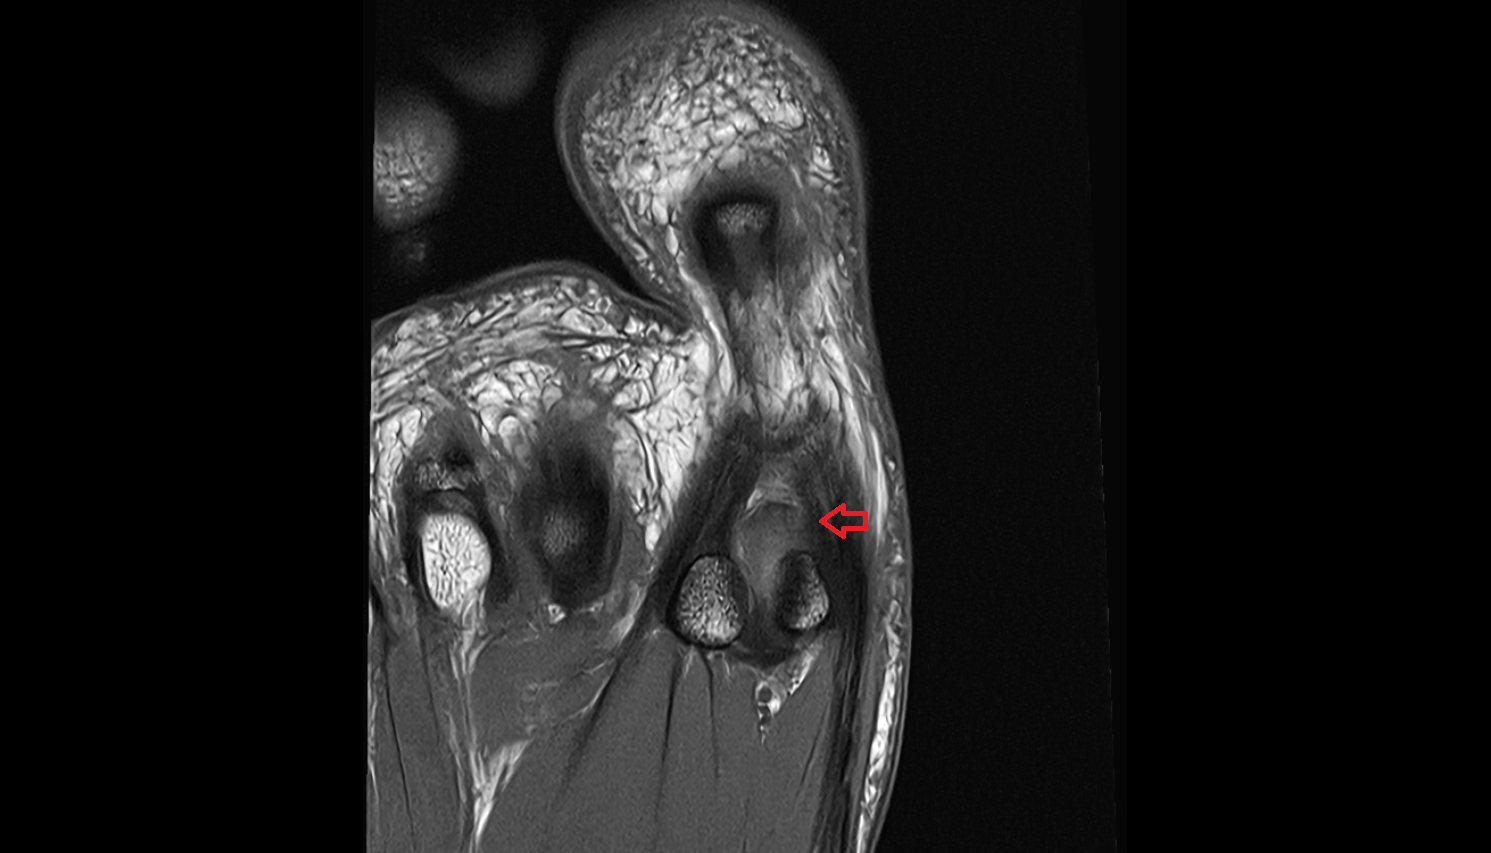

- Temporomandibular joint

- Mandibular condyle

- Mandibular fossa

- Articular disc of temporomandibular joint

- Articular eminence

- Intermediate zone of articular disc

- Lateral temporomandibular ligament